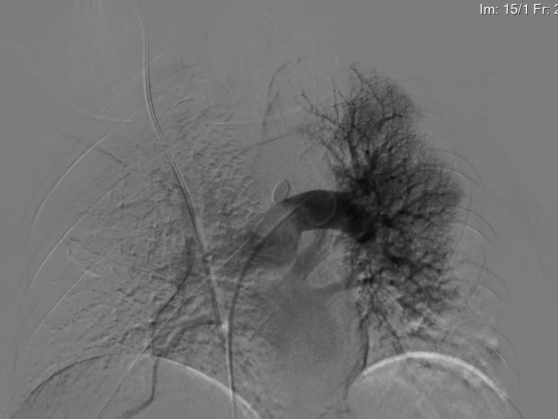

在DSA(血管造影机)的实时精准引导下,何春水主任团队通过患者大腿根部的微小穿刺点,将一根纤细的导管精准送达肺动脉。造影显示,患者的左下肺动脉主干、右中肺动脉主干已被大块血栓完全堵塞,血流中断!

专家们小心翼翼地将一种特殊的“多层饼网状支架”输送到血栓部位,精准释放。这种支架像一张柔韧的网,能够牢牢地包裹住血栓。随后,专家们缓慢而稳定地回撤支架,重复操作,完整地取出了堵塞血管的血栓!

经过两个小时的奋战,手术屏幕清晰地显示,堵塞患者的肺动脉的血栓被完全清除,左下肺动脉、右中肺动脉血流恢复畅通!术后,患者胸闷症状立即得到缓解,血氧饱和度迅速回升,转危为安。